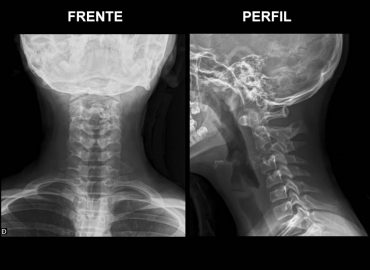

Caso clínico: Varón de 14 años. Motivo de consulta: Tortícolis de comienzo brusco -> luego de estar en cama / […]